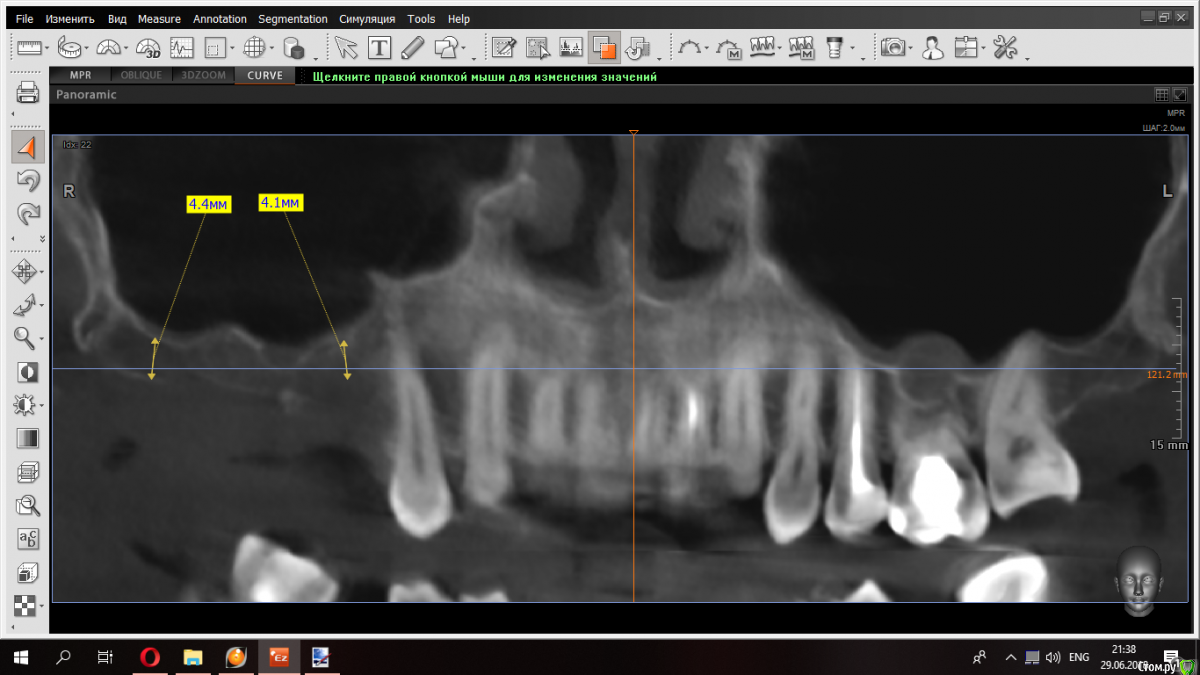

kramer Опубликовано 29 июня, 2018 Поделиться Опубликовано 29 июня, 2018 (изменено) Уважаемые коллеги, надеюсь на ваш совет по этому случаю. Какому способу аугментации вы бы отдали предпочтение? ОСЛ + НКР по вертикали с титановой сеткой? Если в области моляров еще можно было бы обойтись только синусов, то в области 15 совсем беда - ни высоты ни ширины. Срез 15Срез 16Срез 17 Изменено 29 июня, 2018 пользователем kramer Ссылка на комментарий